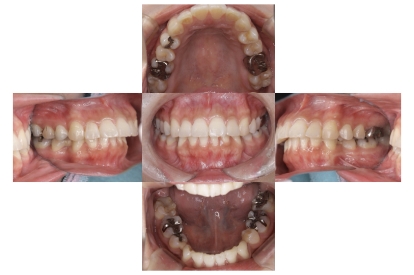

症例1

上顎前突、叢生

抜歯

ブラケット矯正

上下顎叢生、上顎前突(出っ歯、上下の前歯のガタガタ)のケースです。

装置はラビアル(上下表側)で、上顎の小臼歯を2本抜歯を行っています。抜歯したスペースを使って、上の前歯の後方移動と叢生(ガタガタ)と出っ歯の改善を行っています。下は歯と歯の間にIPR(隣接面削合)を行い、スペースを確保し、叢生の改善を行っています。

主訴 前歯のガタガタと出っ歯が気になる。

年齢・性別 47歳 女性

お住まいの地域 神奈川県川崎市

治療方針 抜歯スペースおよびIPRを利用して上前歯の叢生(ガタガタ)の改善

抜歯部位 上顎左右第一小臼歯

使用装置 ラビアル(上下表側)、顎間ゴム

治療期間 2年0か月

治療回数 15回

リテーナー クリアリテーナー

BEFORE

AFTER